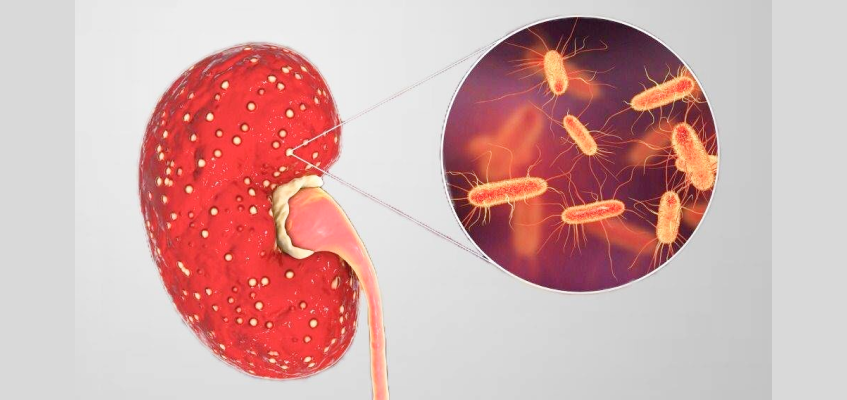

ПИЕЛОНЕФРИТ

или нефрит почек – воспалительное поражение почечной ткани и лоханки почки. Существуют две стадии: острая и хроническая (бессимптомная в 70% случаев). При остром пиелонефрите поражается, в основном, канальцевая система почки. Наиболее частой причиной перехода воспаления в хроническую форму – пиелонефрит, недолеченный в острой стадии с сохранением очага инфекции, порой, на всю жизнь. Даже незначительный сбой в работе иммунной системы может провоцировать обострение пиелонефрита. При этом будут воспаляться всё новые участки почечной ткани, что приведет к ее сморщиванию. Если процесс двусторонний – есть риск развития ХПН.

Причины возникновения пиелонефрита:

нарушения оттока мочи;

снижение иммунитета;

наличие камней или опухолей в почках;

аденома;

хронические заболевания кишечника;

подагра, сахарный диабет.

АПОСТЕМАТОЗНЫЙ ПИЕЛОНЕФРИТ

Причины апостематозного пиелонефрита

- бактериальная инфекция в канальцах, лоханке и мозговом веществе почек, распространяющая по восходящему (извне) или нисходящему пути (с током крови или лимфы из очага воспаления в организме).